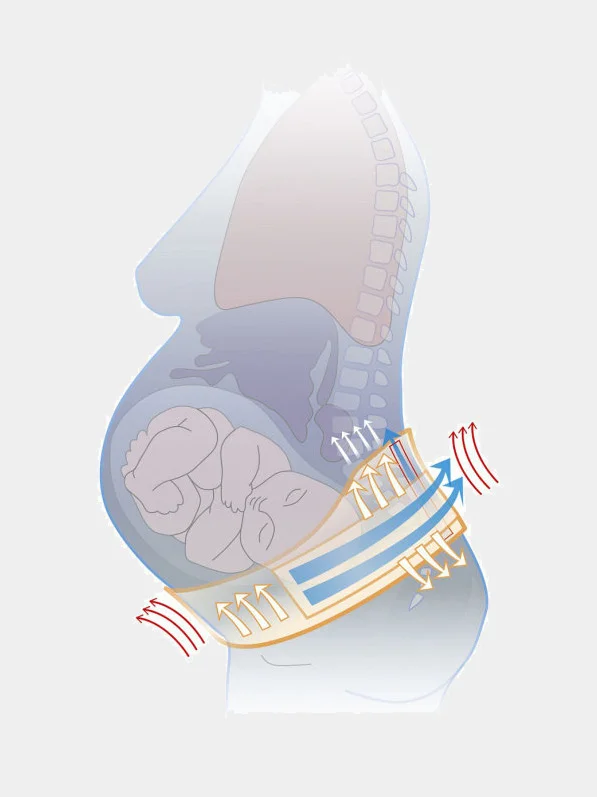

- поддерживает живот во время беременности и в ранний послеродовый период

- снимает нагрузку с пояснично-крестцового отдела позвоночника, уменьшает боли в пояснице

- предохраняет ткани передней брюшной стенки от чрезмерного растяжения

- обеспечивает правильное положение плода в матке, предотвращая преждевременное опускание

- позволяет сохранить оптимальный уровень повседневной активности во время беременности и правильный ортопедический режим